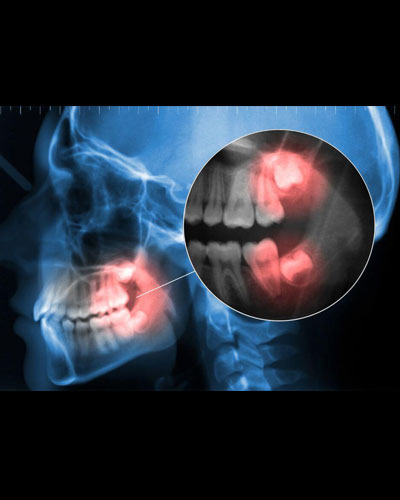

Làm tiêu xương hàm, viêm tủy, mất răng kế bên

Phòng nha vô trùng – Chụp phim 3D định hướng an toàn tuyệt đối